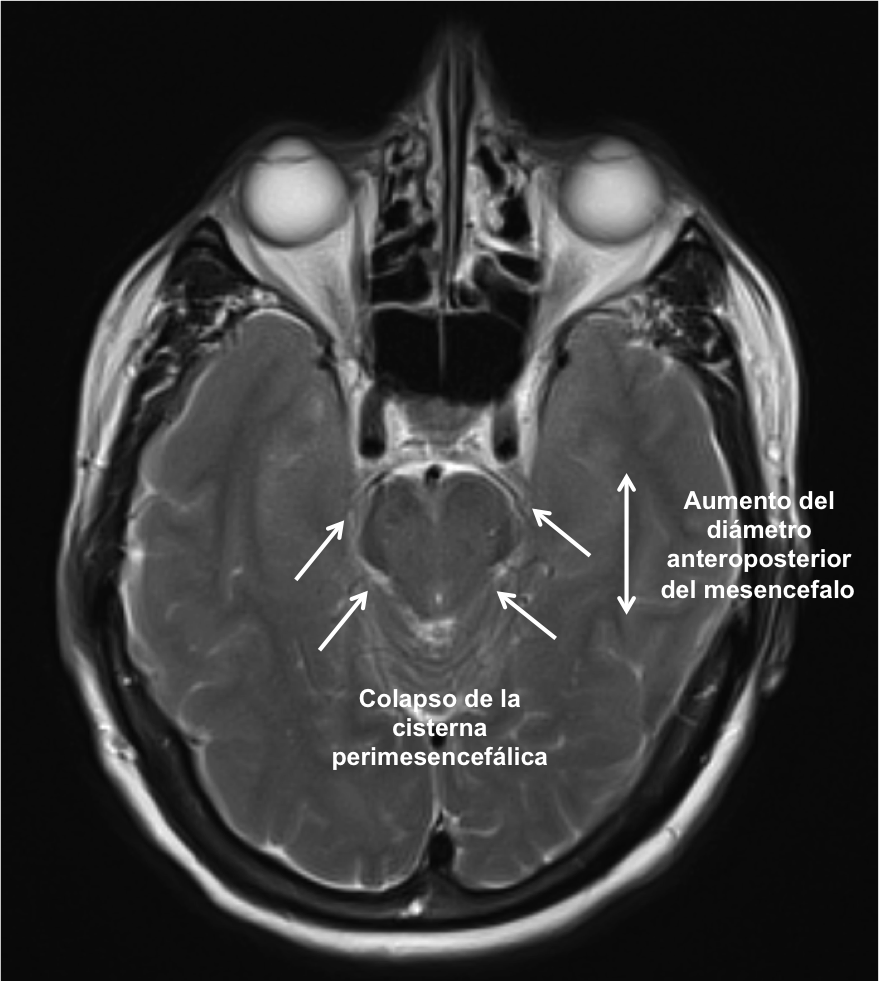

En la Imagen 3, el descenso del cerebro produce un colapso de las cisternas basales y un aumento del diámetro anteroposterior del mesencéfalo.